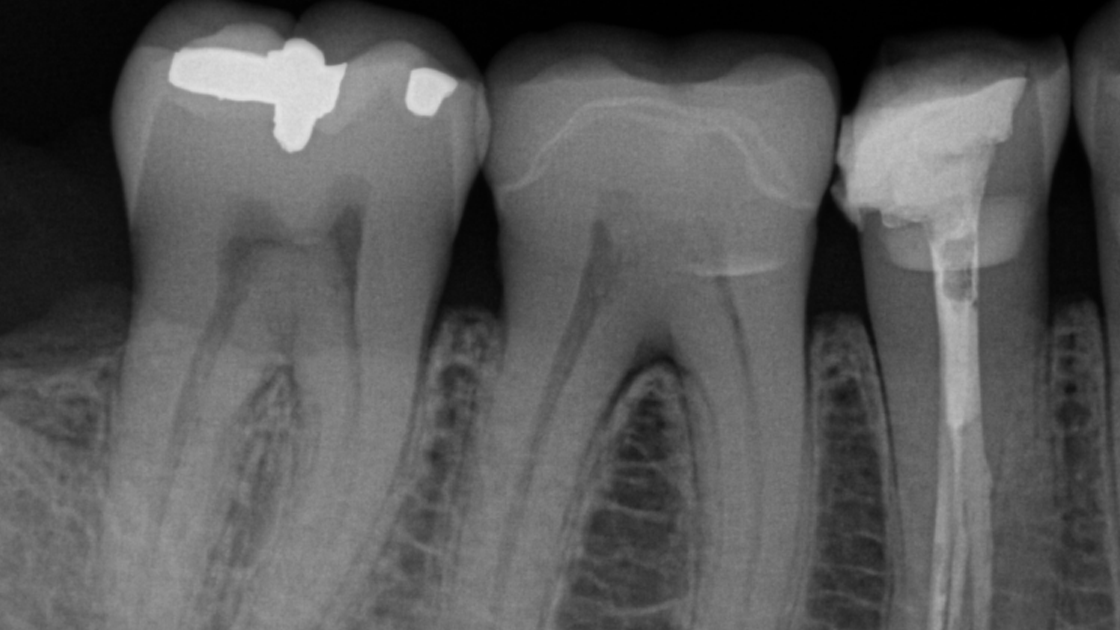

Ya sea que necesite imágenes radiológicas intraorales para evaluar un área sintomática o un tratamiento endodóntico continuo, la gama de productos intraorales de Dentsply Sirona tiene la solución adecuada para brindar soporte a su flujo de trabajo. La cartera de imágenes radiológicas intraorales se diseñó para ayudarlo a alcanzar la precisión en sus capturas de radiología, especialmente cuando se trata del posicionamiento de su sistema. Nuestros productos de imágenes radiológicas intraorales también están optimizados para una integración sencilla y flujos de trabajo simplificados, gracias a una digitalización de última generación y una automatización de flujo de trabajo eficientes. Gracias a su conexión con Sidexis 4 y DS Core, las soluciones le permiten ingresar al universo digital de Dentsply Sirona y aprovechar todos los beneficios de esta plataforma en evolución.